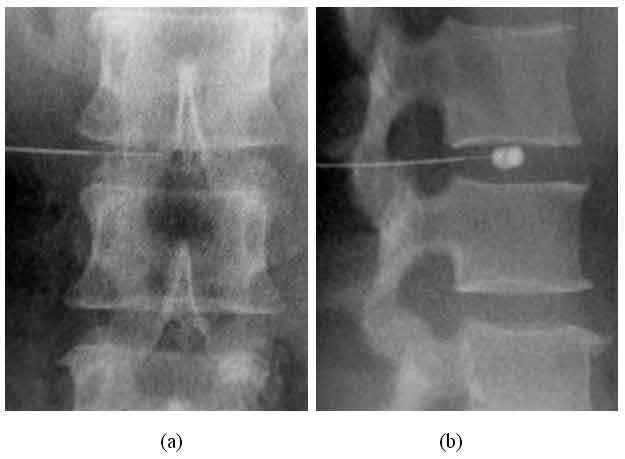

Negli ultimi anni, tuttavia, i ricercatori hanno indagato sul suo potenziale antidolorifico contro l’ernia del disco, un problema di infiammazione o danneggiamento dei dischi della colonna vertebrale che normalmente agiscono come ammortizzatori per il corpo. Questo provoca dolore e intorpidimento. Di solito il trattamento comporta fisioterapia e antidolorifici, ma molte persone finiscono per sottoporsi a interventi chirurgici. La terapia a base di ozono potrebbe aiutare tutti a evitare di finire in sala operatoria. Gli scienziati tedeschi hanno trattato i pazienti resistenti ai trattamenti con una singola iniezione di ozono. Ebbene, il 37 per cento dei soggetti ha riferito di non avere alcun dolore sei mesi dopo l’iniezione del gas. Un terzo dei pazienti, invece, ha segnalato episodi meno frequenti di mal di schiena, di solito una volta al giorno. Il 22 per cento, infine, non ha risentito di alcun miglioramento e il 7 per cento ha dichiarato che la situazione e’ peggiorata. Prima di diventare un trattamento il gas viene mescolato con farmaci steroidei che aiutano a smorzare l’infiammazione e poi viene iniettato direttamente nel disco danneggiato con un anestetico locale. Scansioni hanno mostrato che i dischi danneggiati si sono ridotti dal 2 al 15 per cento.